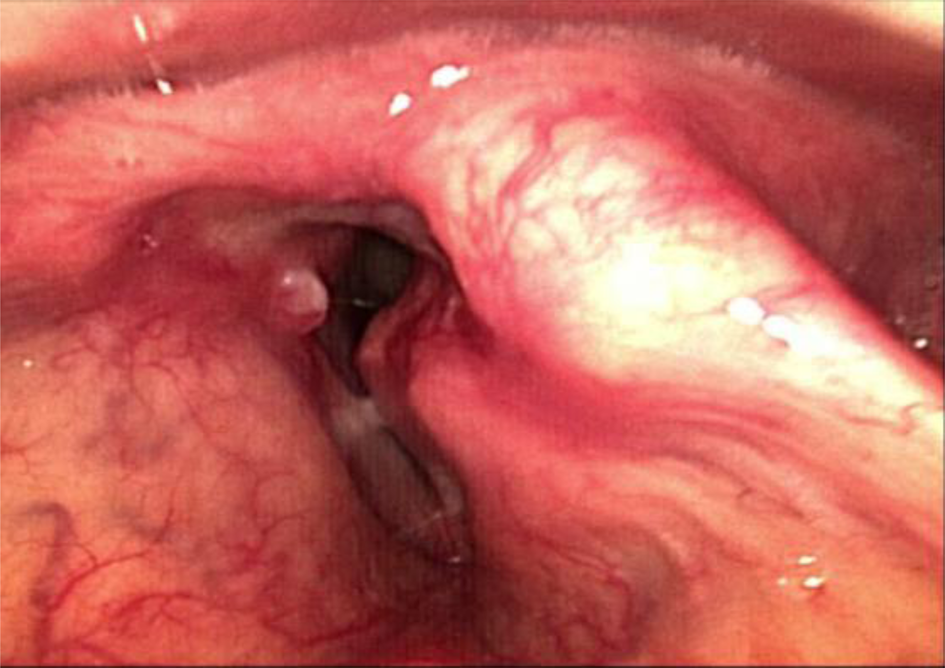

A 49-year-old otherwise healthy male teacher presented to a general hospital with hoarseness and stridor that had slowly progressed over 12 months. On digital flexible laryngoscopy, a supraglottic submucosal mass was seen at the site of the left arytenoid (Figure 2). A magnetic resonance imaging scan showed enlarged left arytenoid cartilage with calcifications, indicative of a chondral tumour (Figure 3).

Fig. 2. Diagnostic laryngoscopy: a tumour is seen on the left side. The lumen is narrow and deviated.